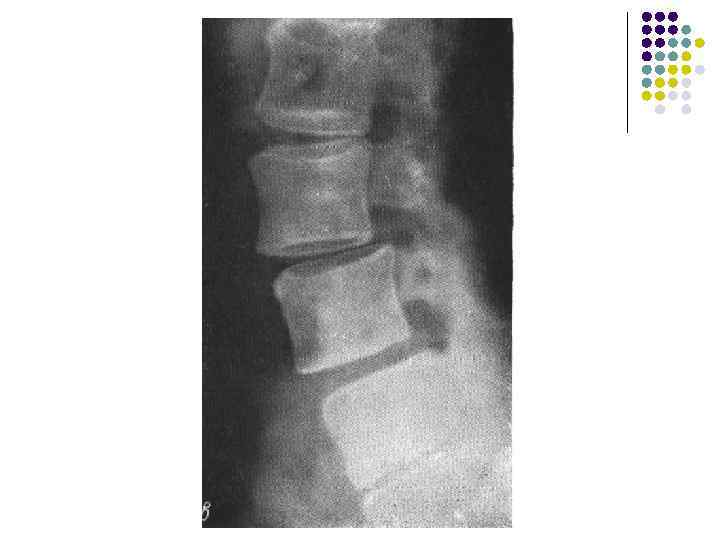

Артроз дугоотростчатых суставов из-за перегрузки. В н/поясничных позвонках может развиваться спондилолистез, подвывих в дугоотростчатых суставах, неоартроз (суставной отросток и ножка дуги) Гипер- или гипо- мобильность – увеличение амплитуды нормальных движений (при функциональных пробах)

l На рентгенограмме грудного отдела позвоночного столба в боковой проекции определяются признаки выраженных, распространенных дистрофических изменений в виде болезни Форестье за счет характерных костных разрастаний под передней продольной связкой практически во всех визуализированных отделах грудной части позвоночника. На этом фоне отмечаются также явления умеренного и также распространенного отсеохондроза – сужение межпозвонковых простанств, субхондральный остеосклероз, соответствующие костные разрастания. Положение тел позвонков правильное, деструктивных изменений нет.